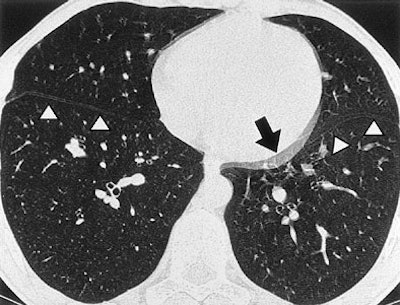

| Tram-track and double cardiac contour artifacts. Non-ECG-gated thin-section CT scans obtained at the same level of the paracardiac parenchyma in a 25-year-old man with spontaneous pneumothorax. Note the double contour artifact seen in the blurred cardiac border (arrow). Tram-track artifacts can be seen in both the right and left interlobar fissures (arrowheads) (Radiology, 1999;212:649-654). |

In a 1999 study, Schoepf and colleagues from the University of Munich in Germany aimed to identify the benefits of prospective ECG triggering for examining the lung parenchyma using high-resolution CT (Radiology, September 1999, Vol. 212:3, pp. 649-654).

"You can see that ECG triggering takes care of those twinkling star artifacts adjacent to the left cardiac border," he said of an image projected on the screen. "You get rid of what has been dubbed the tram-track sign, the double appearance of the (lung) fissures, and the double cardiac border."